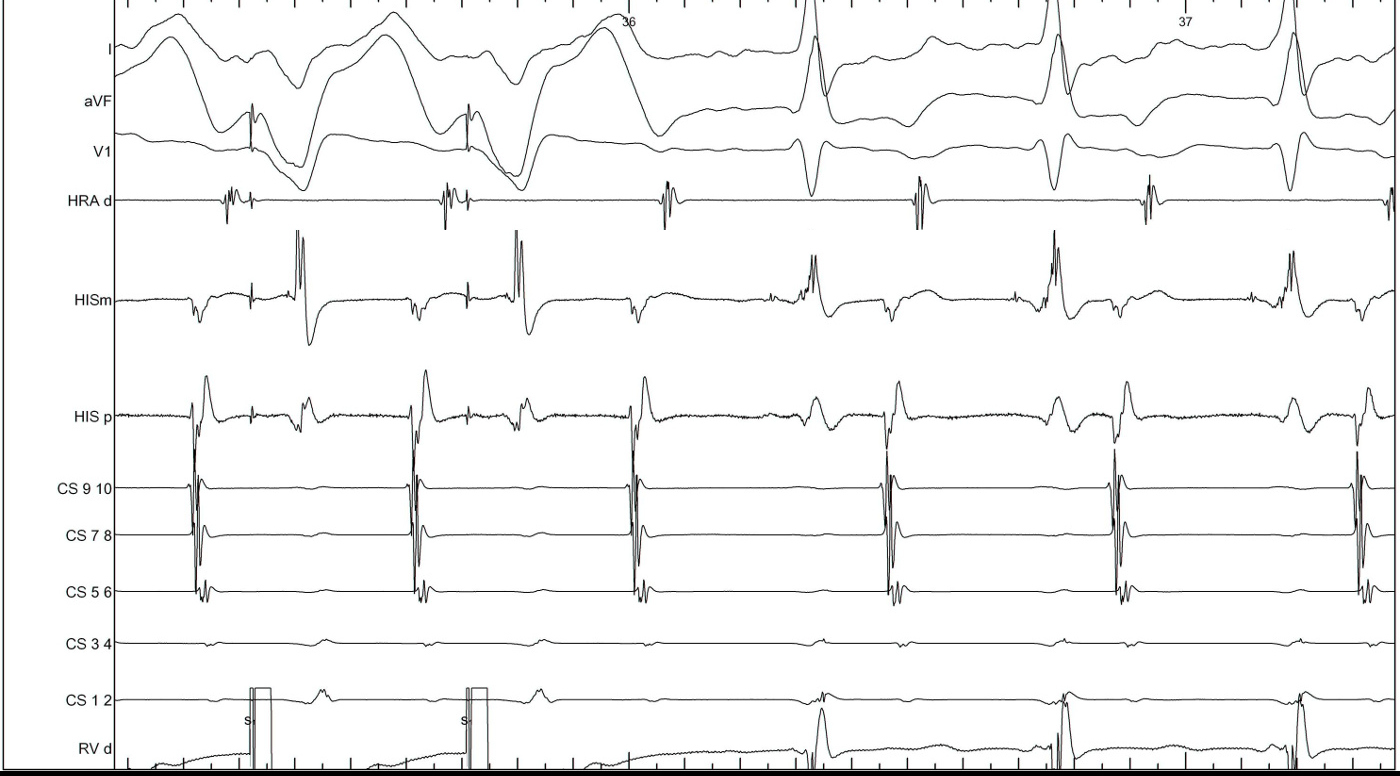

Ventricular overdrive pacing

vav_avnrt.jpg

• Sequence - VAV or VAAV

Response

• Atrium not entrained - AT / AVNRT

• VAAV - AT

• VAV - AVNRT